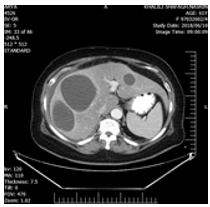

In treatment history, a shoulder Pain was present which not associated with any trauma or GI tract problem. That time she was conscious, only complaining of severe shoulder pain and mild abdominal pain. The shoulder movement was normal. The only physical finding was mild tenderness and guarding in all quadrants of the abdomen. Her blood pressure120/80 mmHg, heart rate was 95 beats min, respiratory rate 18 bpm, WBC=21000. Three days after admission, she had a CXR showed that shoulder joint was normal but in chest mild pleural effusion and atelectasis was present with on the right side. The patient underwent ultrasonography which showed one intact cystic lesion (42x38mm) in the left lobe and two cysts in the right lobe (87x83mm) and (67x4 mm) and computed tomography of abdomen showed as U&S but showed fluid at sub diaphragmatic location and around with on liver (Figures 1-3).

Figure 1: CT-scan of patient show three intact cystic lesions in the right and left lobes with mild effusion in around the liver.